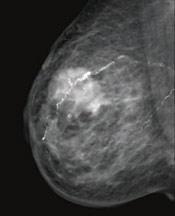

July 15, 2011 — According to a new report by iData Research, the European women's health market is valued at over $917 million, and is estimated to reach $1.1 billion by 2017. This is largely due to recovery of the digital breast imaging, OB/GYN ultrasound imaging and female sterilization segments. Implementation of national breast screening programs by European health authorities is expected to counteract the negative effects of the global economic crisis, resulting in double-digit growth of the European digital mammography market by 2017.